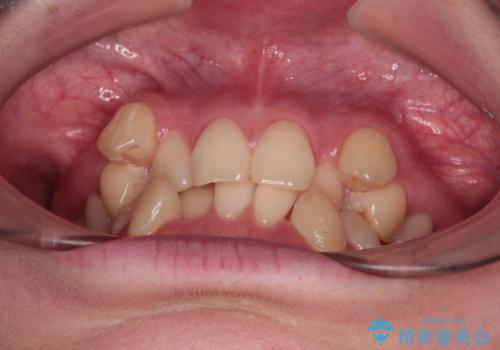

上下の八重歯とクロスバイト ワイヤー装置での抜歯矯正

- 八重歯とクロスバイトを気にして来院された患者様です。

上下ともに八重歯が顕著であり、前歯のクロスバイトがあったため、上下左右の第一小臼歯4本を抜歯し、ワイヤー装置での抜歯矯正を行うこととしました。